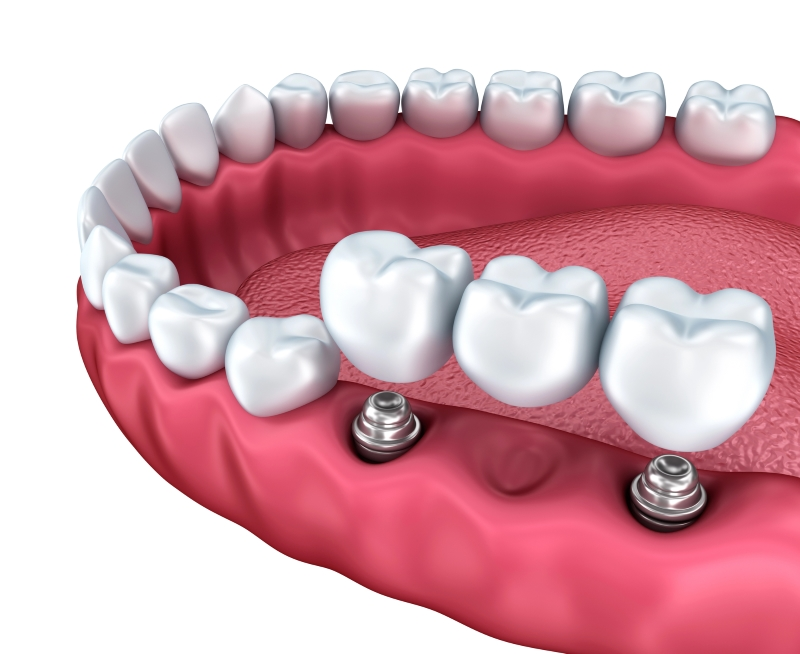

Step 2: Implant Placement

The zirconia implant is precisely placed into the jawbone using minimally invasive techniques that promote quick healing. By using advanced techniques, we aim to reduce discomfort and accelerate the recovery process.

Step 3: Healing & Osseointegration

Over several months, the implant naturally fuses with the jawbone, creating a secure foundation for the final restoration. This process, known as osseointegration, is crucial for ensuring long-term stability and durability.

Step 4: Final Restoration

A custom-made ceramic crown is placed on the implant, completing your natural-looking and functional smile. The final restoration is carefully crafted to match the shape, size, and color of your natural teeth for seamless integration.